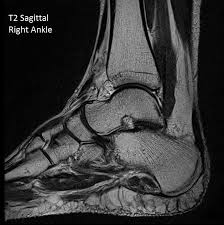

From start to end, an mri acquisition can take 15 to 90 minutes. Because of limited blood flow to the ligaments of the ankle, more severe injuries may take between three and six months to heal. This may include the ankle, foot, and surrounding tissues. You will not be able to feel the magnetic field or the radio waves. A leg mri (magnetic resonance imaging) scan of the leg uses strong magnets to create pictures of the leg.

A leg mri (magnetic resonance imaging) scan of the leg uses strong magnets to create pictures of the leg. Your doctor has recommended you for an mri of your leg. Mris are not typically performed for ankle fractures but may be part of a more detailed examination by an orthopedic surgeon. How long does the mri take? Healing from a high ankle sprain can take anywhere from six weeks to three months — sometimes even more.

If you are dealing with a normal sprained ankle, you shouldn't have to wait too long until you're healthy again. You'll be given earplugs or headphones to wear. A leg mri (magnetic resonance imaging) scan of the leg uses strong magnets to create pictures of the leg. Indeed, the larger the field of view scanned, the longer time it will take to acquire quality images. When examining the ankle joint, the coil is placed directly on the test joint.

Depending on the size of the area being scanned and how many images are taken, the whole procedure will take 15 to 90 minutes.

You will not be able to feel the magnetic field or the radio waves. We scan axial (top to bottom) sagittal (right to left) and coronal (front to back). Some people have trouble being in an enclosed space for this time, and you can talk to your doctor about if an open mri. On average, the procedure lasts from 30 to 40 minutes. We are taking hundreds, sometimes thousands of images and it takes the machine several minutes to acquire these slices. How long does it take to heal a broken ankle? Ct scans can reveal more detail about the bones of the joint. Because of limited blood flow to the ligaments of the ankle, more severe injuries may take between three and six months to heal. A leg mri also creates pictures of the knee. From start to end, an mri acquisition can take 15 to 90 minutes. This may include the ankle, foot, and surrounding tissues. It will be necessary for you to remain as still as possible, however, and some people find this stillness difficult to maintain for the duration of the scan. The images can be stored on a computer or printed on film.